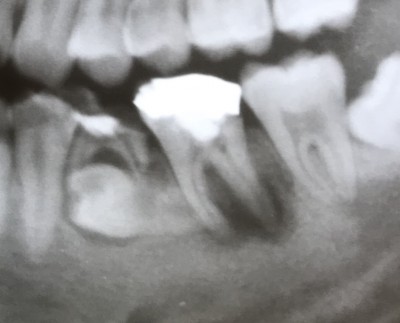

【下顎第二大臼歯】根管治療2年経過

2023.06.18 症例紹介